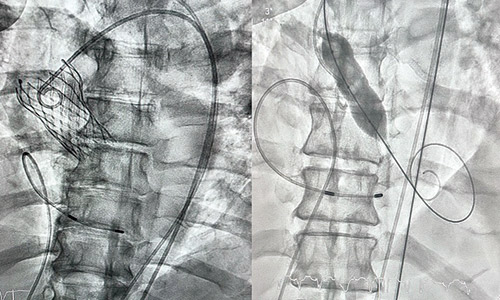

وأجريت عملية التغيير تحت التخدير الموضعي دون الحاجة للتخدير الكامل، حيث قام الفريق الطبي بتجاوز الصمام المتضيق وزراعة صمام جديد عن طريق القسطرة القلبية عبر فتحة صغيرة في الفخذ الأيمن، وبعد زراعة الصمام زادت مساحة الفتحة الخارجية له إلى «2.4» سم مربع، وانخفض ضغط الدم إلى المعدل الطبيعي، وكذلك تحسنت وظائف القلب وضغط التجويف الداخلي، وهو ما أدى -بفضل الله- إلى استقرار حالة المريض، ومغادرته للمستشفى بعد «24» ساعة. ووصف د. الحجيلي العملية بأنها عملية نوعية لاعتبارات السرعة الكبيرة التي تمت بها مرحلتي التشخيص وإجراء العملية، إضافة إلى الدقة العالية والاحترافية التي نفذت بها كامل الخطة العلاجية، علاوة على استخدام أحدث تقنيات زراعة الصمامات التي أغنت عن الجراحة، كما أن التخدير الموضعي ساهم أيضاً في تسهيل المهمة وقلل من المخاطر، وأغنى عن التنفس الصناعي، وأضاف د.الحجيلي: «أستطيع أن أقول بكل ثقة أن هذه العملية تمت وفق أحدث ما توصل له العالم في مجال التعامل مع حالات تضيقات الصمامات والشرايين».